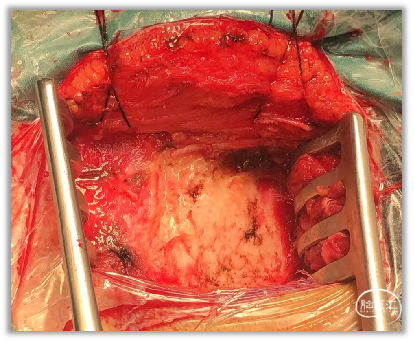

▼6.可留取适当大小肌肉筋膜,用于术毕缝合修补硬膜。

▼7.用单极沿肌肉附着点切开肌肉,保留窄条筋膜便于术毕缝合,用骨膜剥离子向下推开骨膜及枕下肌肉。